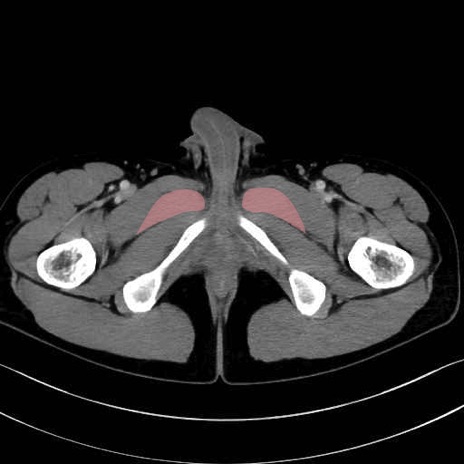

短内転筋(Adductor brevis) のCT画像の解剖

短内転筋 (Adductor brevis)